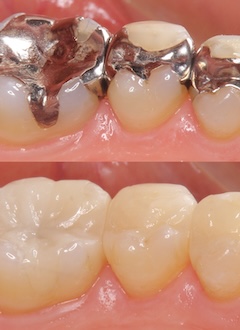

セレック(CEREC)

質の高いセラミックで即日治療

歯の詰め物・被せ物では、1世紀以上の歴史がある世界的な医療メーカーの手がける「セレック(CEREC)」により、質の高いセラミックで即日治療を実現します。

治療部分の衛生面が保たれるだけでなく、治療時間、通院回数を削減します。